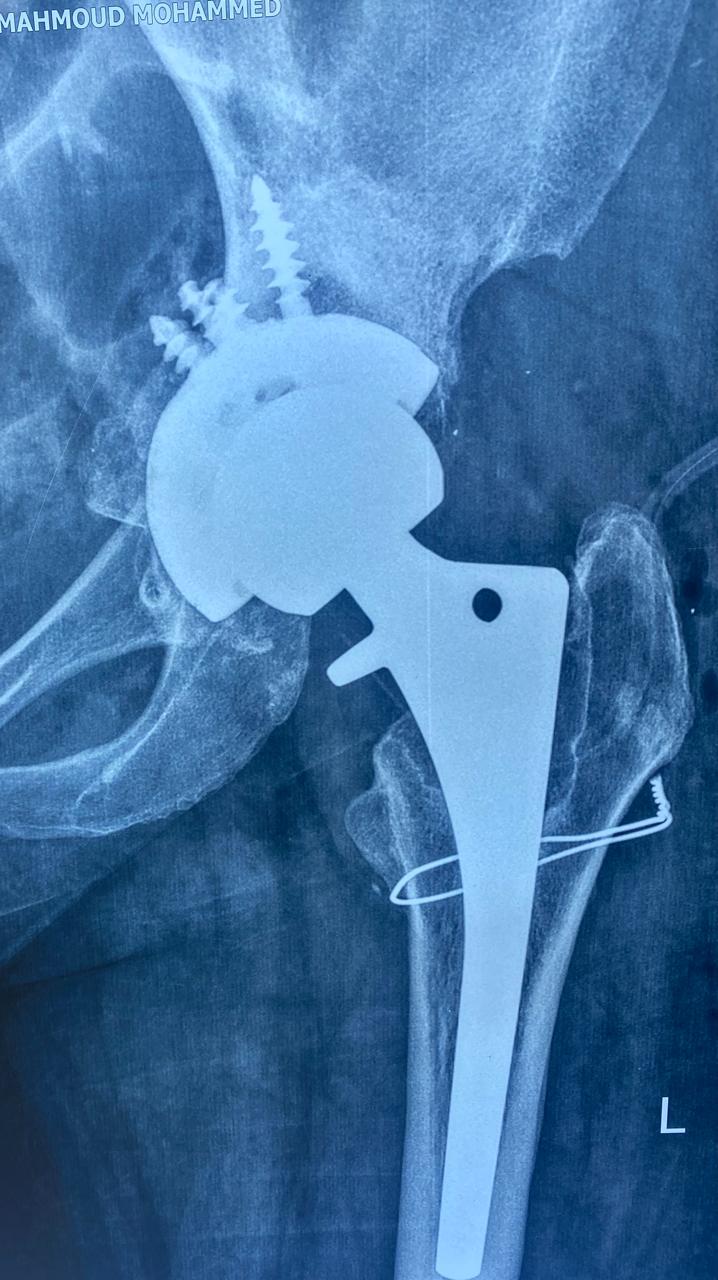

بعد اجراء جراحة تغيير للمفصل مع ترقيع عظمي من بنك العظام

تبين الأشعات ملء الفجوات بالترقيع العظمي.